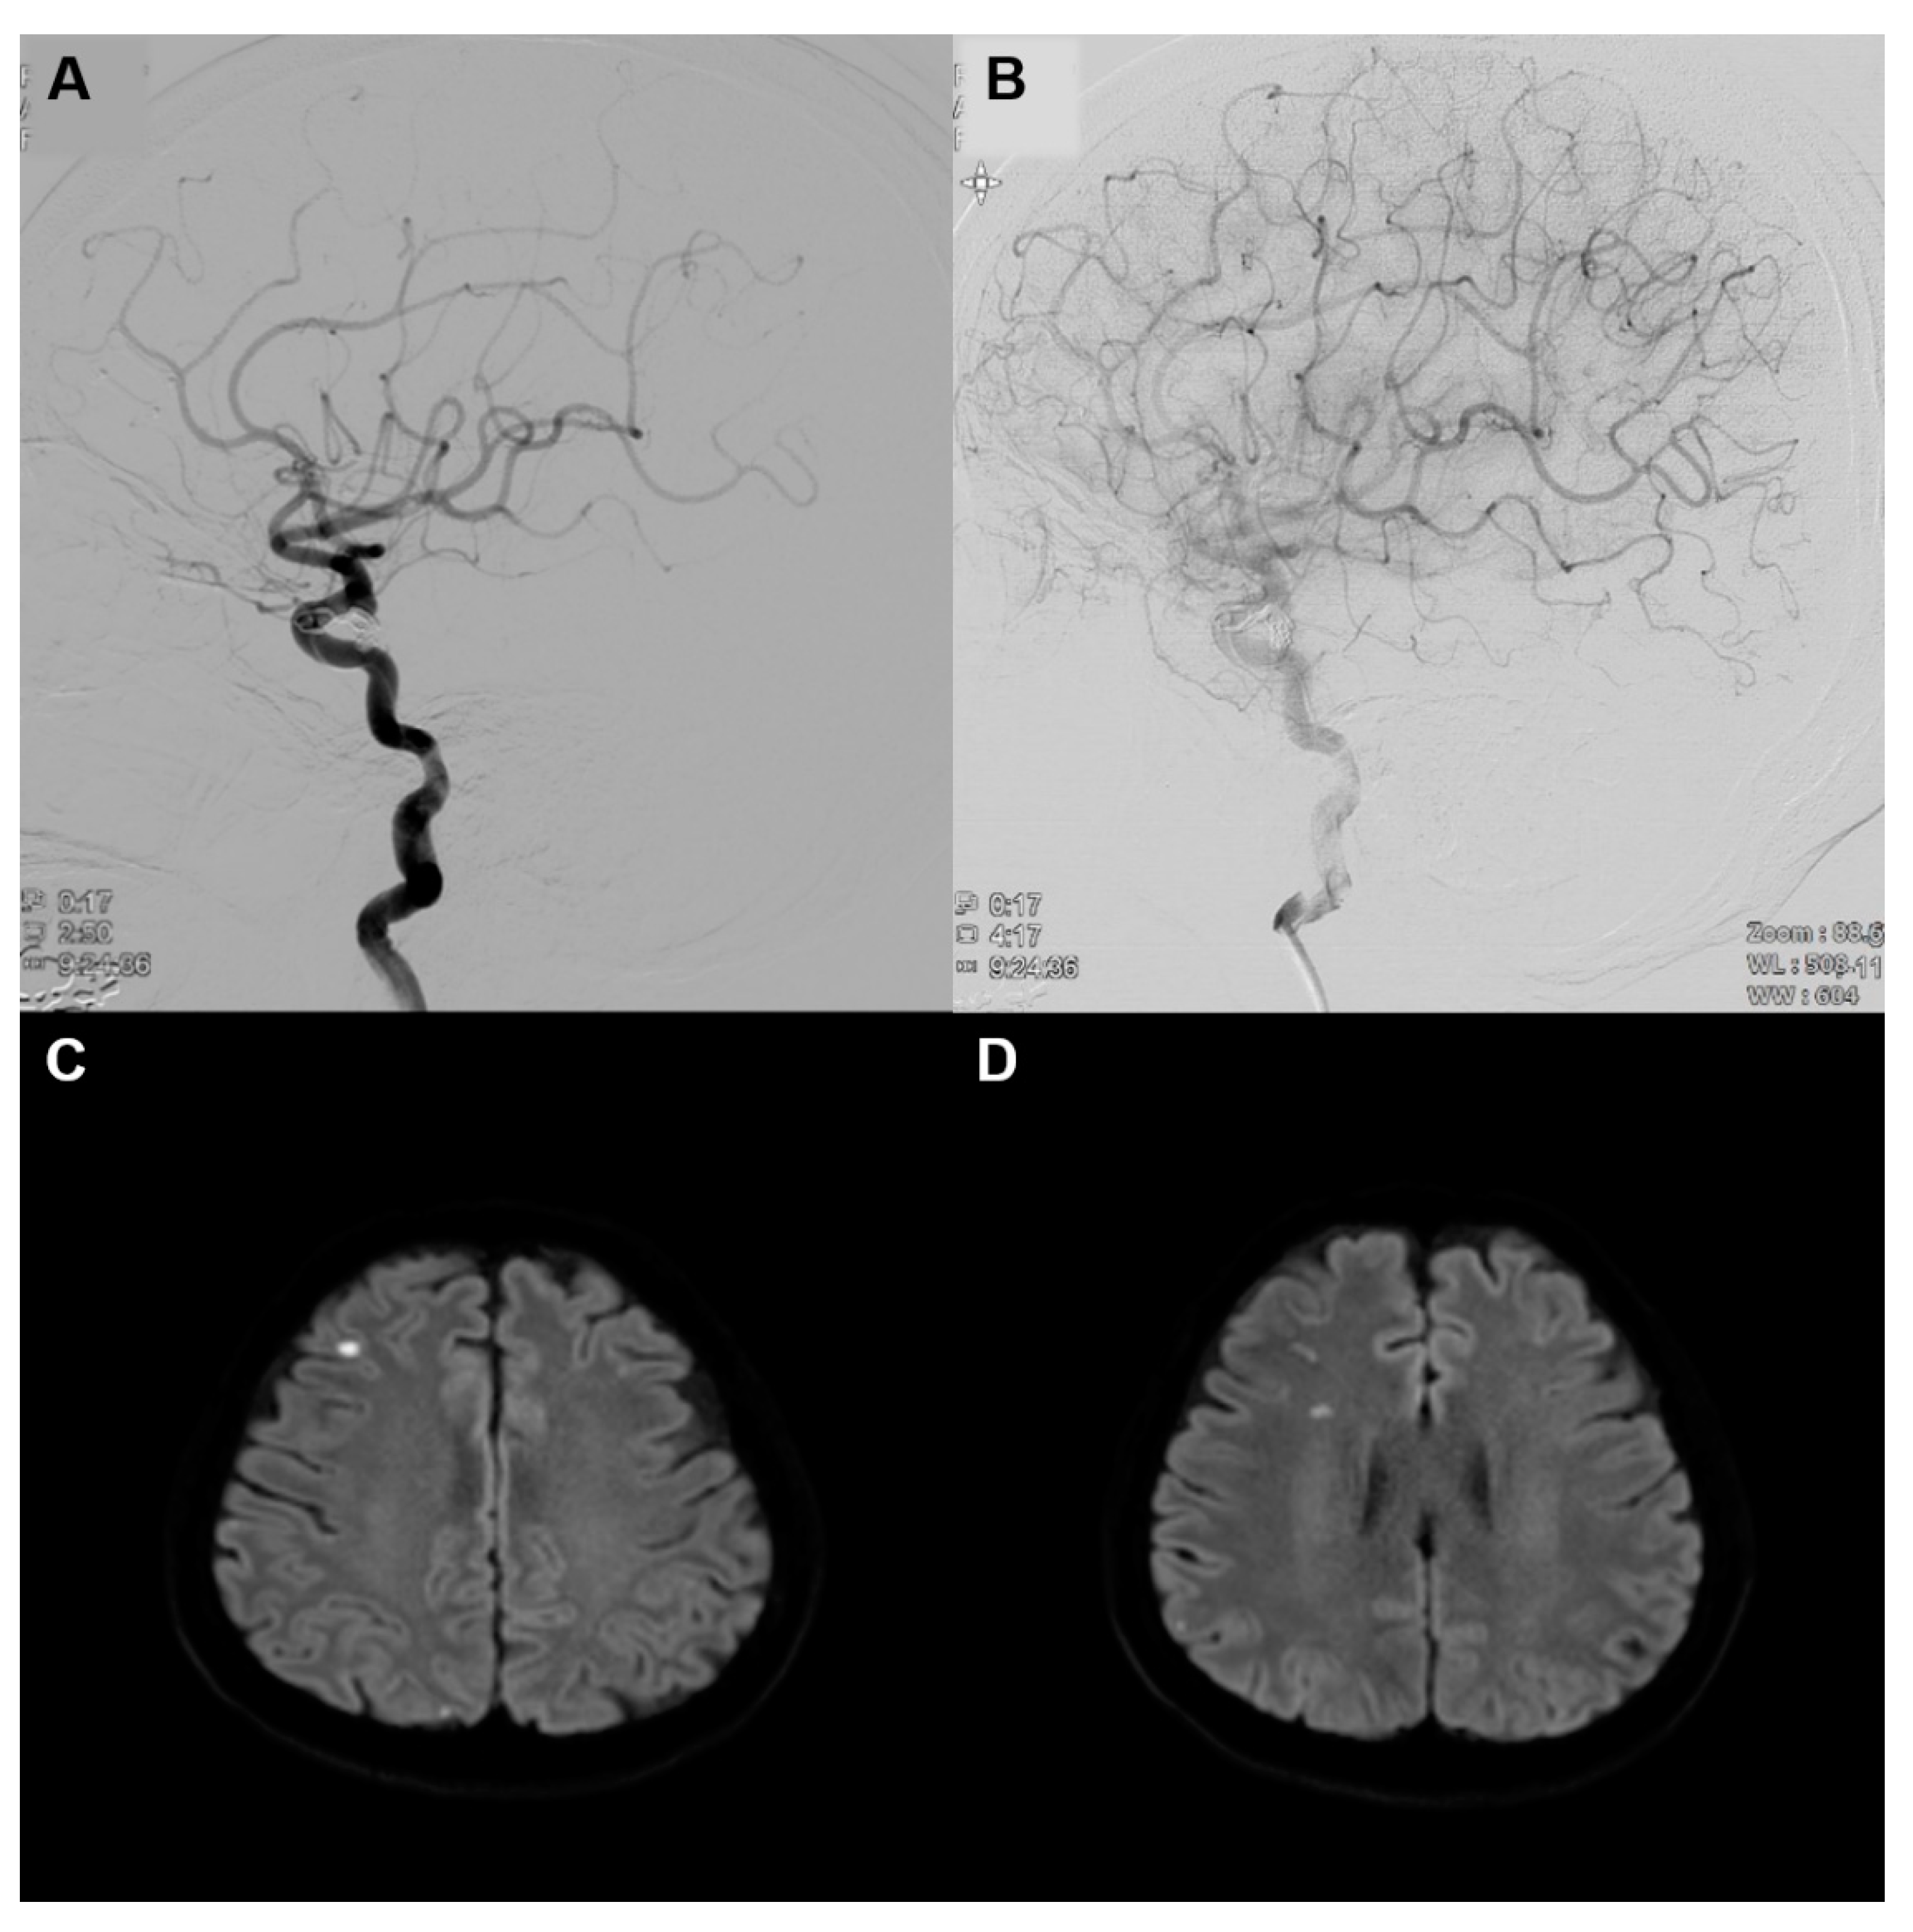

2. Case Presentation